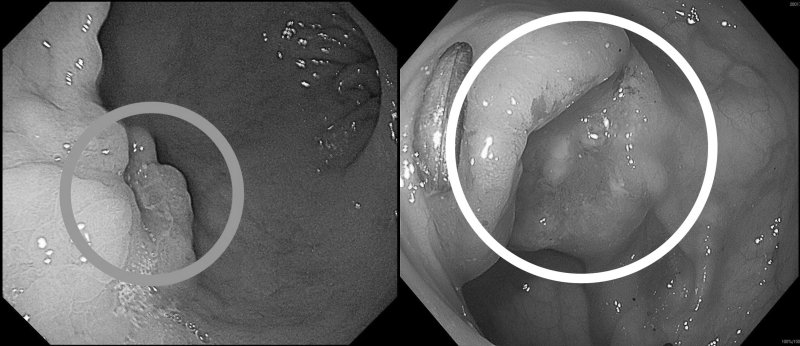

高醫岡山醫院一般及消化系外科主任吳柏宣指出,張先生因突發上腹悶痛、糞便變黑至急診就醫,檢查後發現胃部有2公分惡性腫瘤,再透過大腸鏡確認乙狀結腸另有3公分腫瘤。所幸兩處皆為可手術根治之病灶。